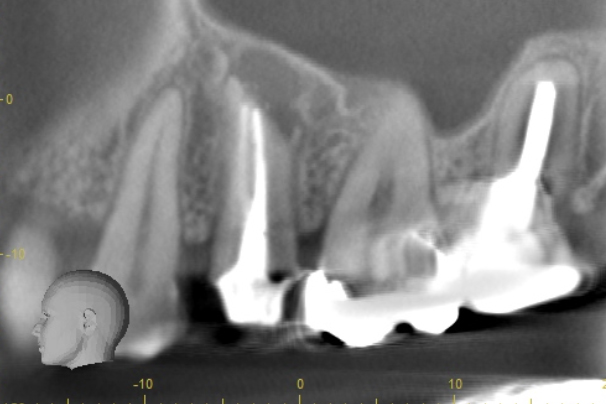

| 根の中にお薬を充填した後のCT画像。やはり根の先に黒い影があるのがわかります。 |

| 根の先の黒い影は消失しました。 | 術後6ヶ月のCT画像です。こちらでも、根の先に黒い影は見当たらないです。 |